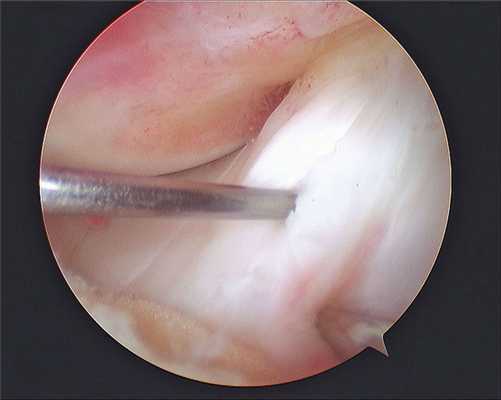

- первым этапом выполняется диагностическая артроскопия сустава, устанавливается характер поражения медиального удерживателя, сопутствующие проблемы с менисками, хрящом. При пластике медиального удерживателя выполняется замещение поврежденной связки аутотрансплантатом.

- при помощи специального инструмента в области «гусиной лапки» выполняется забор аутотрансплантата сухожилия подколенной мышцы (полусухожильная или нежная).

- далее выполняется 2 разреза: один по медиальному краю надколенника, второй в проекции медиального мыщелка бедра. По медиальному краю устанавливаются два якорных фиксатора (расходный материал). Аутотрансплантат фиксируется на эти якоря, свободные концы проводится под кожей, и помещается в сформированный канал в медиальном мыщелке бедра. Фиксация на бедре при помощи биокомпозитного винта (расходный материал).